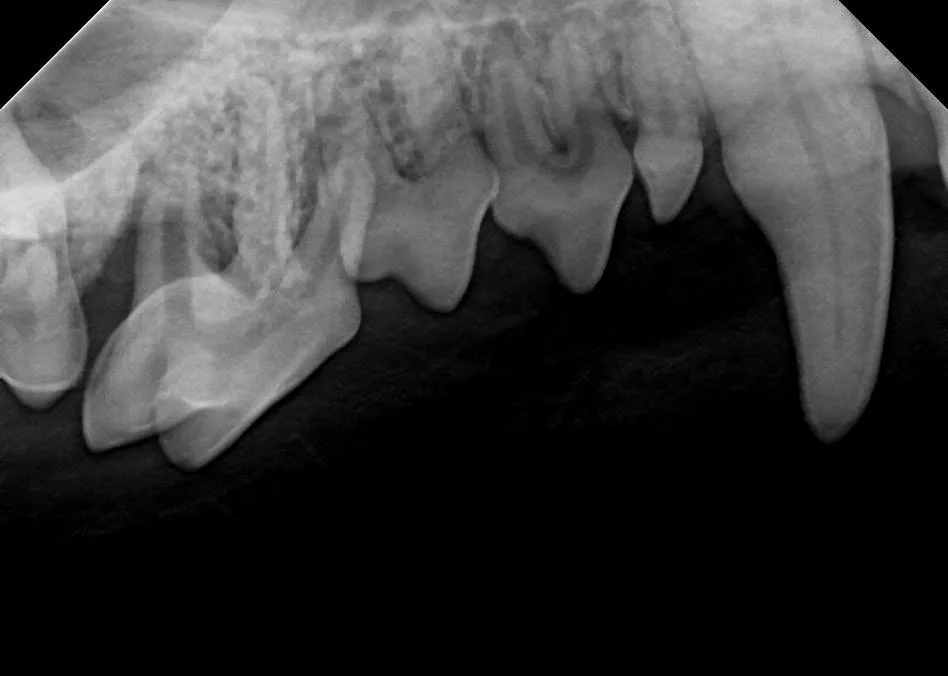

Approximately 25% of dogs are presented with one or more fractured teeth, and 10% have a complicated crown fracture indicating the pulp canal is exposed (Figure 1).4-6 Once exposed to the oral cavity, the canal pulp becomes contaminated, infected, and necrotic, eventually resulting in periapical infection and pain. An oral examination of the patient while under general anesthesia can detect exposed canal pulp; a dental explorer will stick or drop into the open pulp. If open pulp is identified, intraoral radiographs are required to assess the periapical tissues (eg, periapical lucency, root resorption) and the size of the pulp canal (eg, may be wider compared to the contralateral tooth; Figure 2). Necessary treatment options for a pulp-exposed, infected tooth include root canal treatment or surgical extraction.

Left mandibular canine tooth root (tooth 304) that had a complicated crown fracture. A periapical lucency, external inflammatory apical root resorption, and a relatively widened pulp canal are present, indicating the tooth has been dead and infected for months. The chronically exposed pulp results in periapical infection and inflammation.